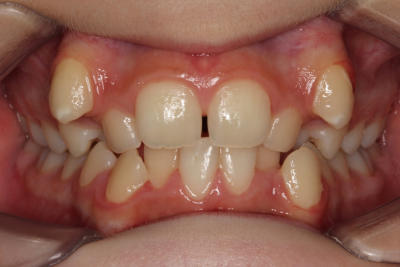

Crowding – Child case